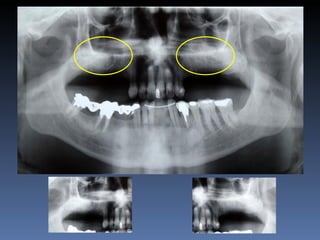

BOX 4 Eusébio Moreno Idade– 73 anos Sexo – Masculino Raça – Caucasiana ASA – II Data- 23-04-2012 Diagnóstico: Desdentado parcial bilateral posterior da maxila. Plano de tratamento: Reabilitação posterior maxilar esquerda, com instalação de 3 implantes endo-ósseos (2.4,.2.5.2.6.), para reabilitação protética fixa.

• 177.

BOX 4 Maria BalbinaGonçalves Idade – 52 anos Sexo – Feminino Raça – Caucasiana ASA – II Data- 27-04-2012 Diagnóstico: Atrofia maxilar vertical posterior bi-lateral; atrofia da pré-maxlia. Plano de tratamento: “Sinus-lift” bilateral , reabilitação da pré-maxila com ROG - regeneração óssea guiada, osso proveniente de Fêmur -Homógeno Fresco- congelado, para instalação de implantes endo- ósseos, e reabilitação protética fixa.